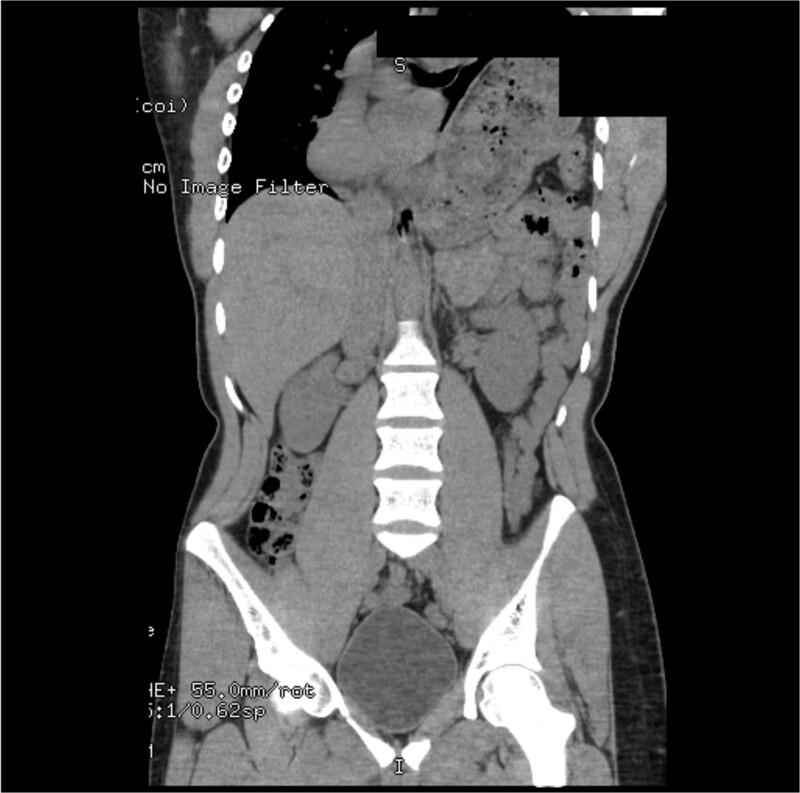

Gastric volvulus has been rarely associated with diaphragmatic paralysis or eventration. In this article, we present the case of a patient with idiopathic paralysis of the left hemidiaphragm that underwent treatment with a robotic thoracoscopic diaphragm plication, which was complicated by massive gastric volvulus resulting in such significant intra-abdominal hypertension that the ipsilateral diaphragm ruptured anterior to the plication suture line.

胃扭转很少与膈麻痹或膈膨出相关。在本文中,我们报告了一例特发性左半膈麻痹患者,该患者接受了机器人胸腔镜膈折叠术治疗,术后并发大量胃扭转,导致严重的腹腔内高压,使得同侧膈肌在折叠缝线前方破裂。